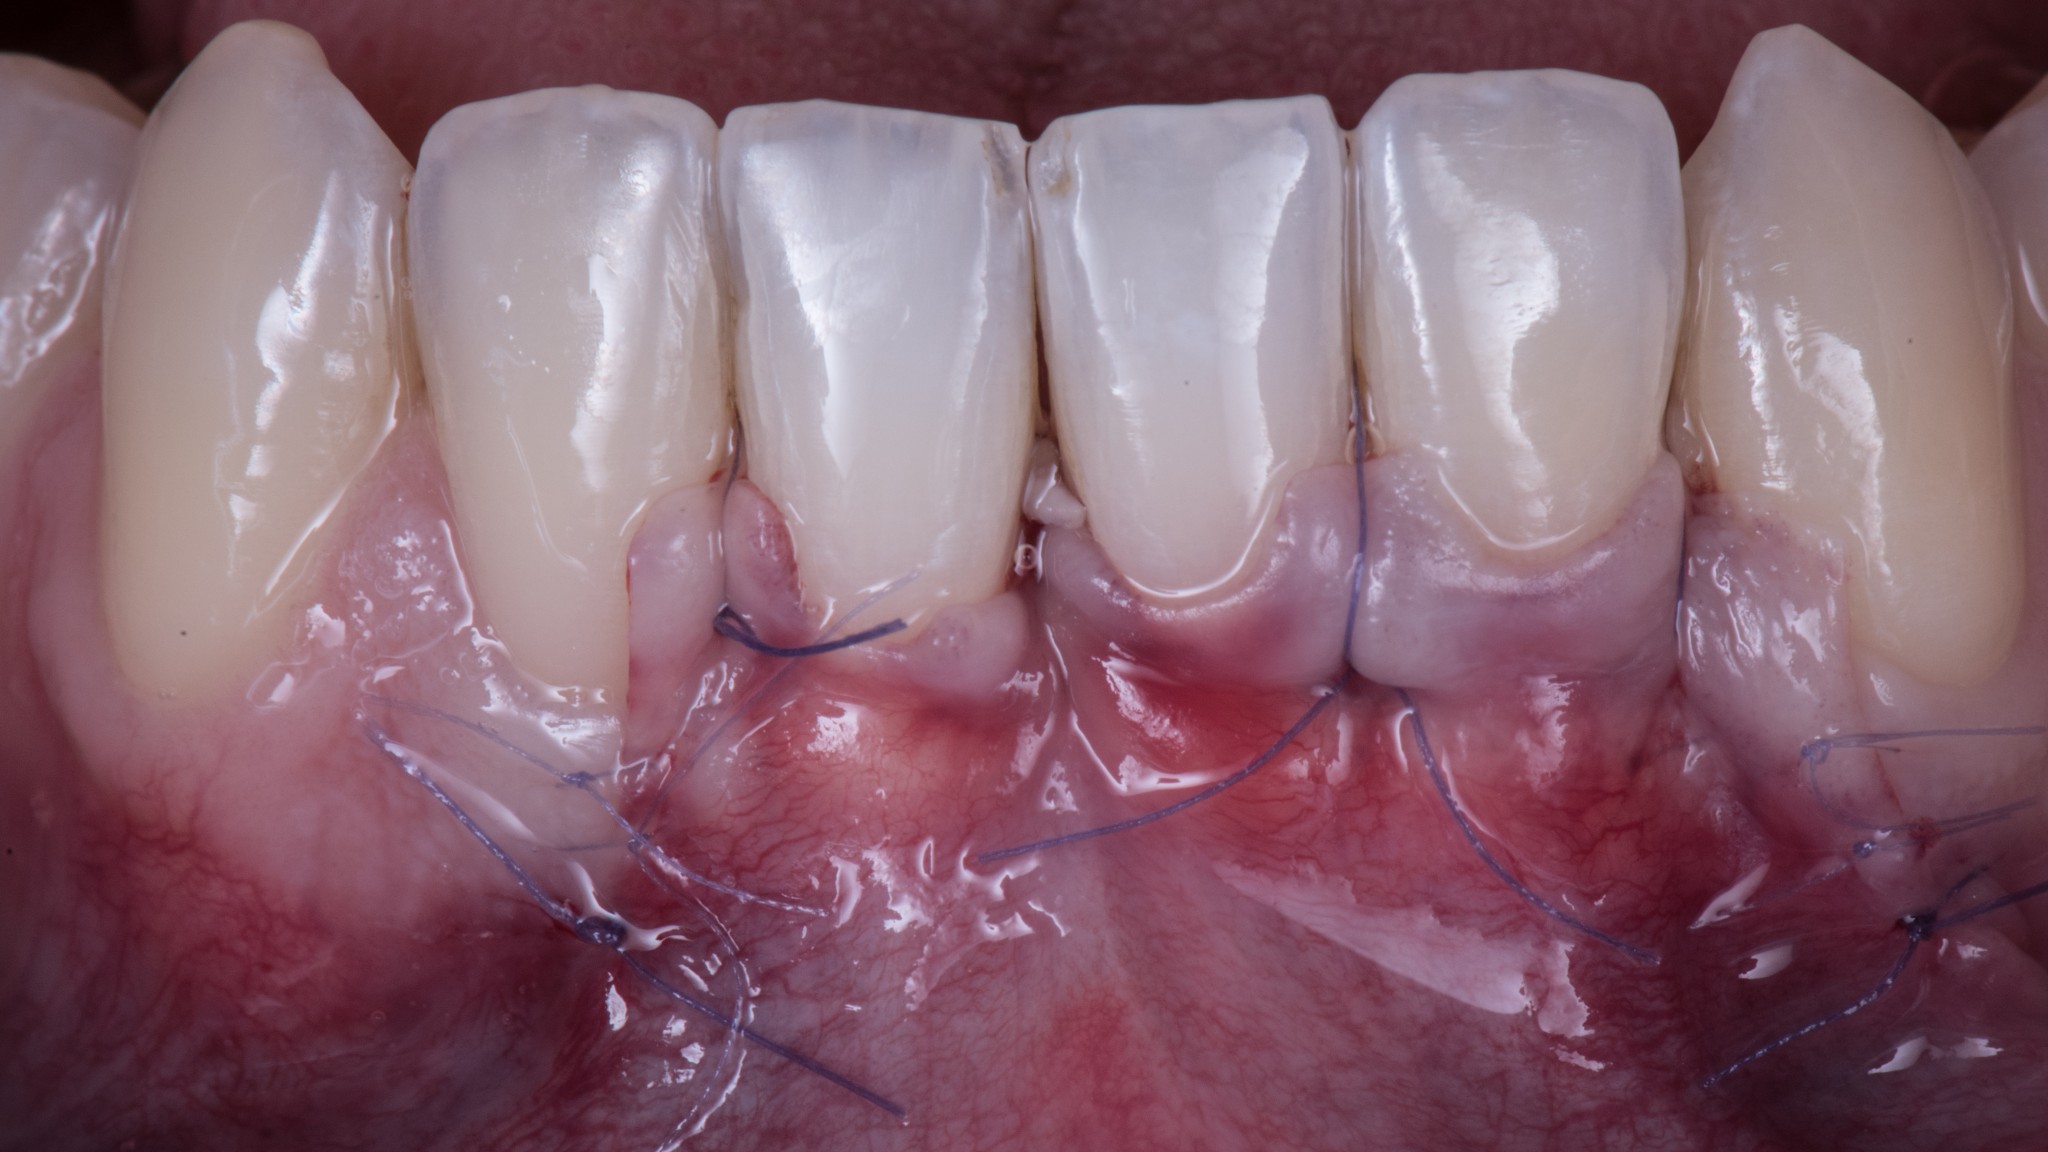

Eccola la tecnica segreta:

dopo aver scollato a tutto spessore per esporre 3mm di cresta ossea, inizia dalla sezione delle fibre superficiali.

Il semplice fatto di anticiparlo semplificherà di molto questo passaggio e ti permetterà di farlo in maniera più pulita e precisa.

Devi solo fare attenzione perché il lembo si assottiglia moltissimo (il che è bene!) e potresti rischiare di perforarlo.

Bando alle ciance, guardatelo nel video!

Questo, associato alle altre due tecniche segrete di cui parleremo nei prossimi articoli, ti consente di arrivare a 15 giorni dall’intervento in questa situazione: